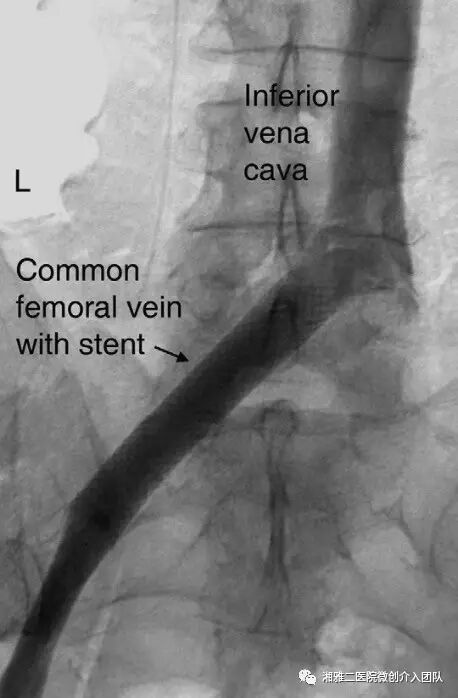

支架植入后

注意: 支架应该超过受压段1cm,比如髂总静脉受压综合症患者,支架的最常见位置为支架头端位于IVC/髂总静脉交汇处上方1cm处。上图的支架实际上位置偏低。